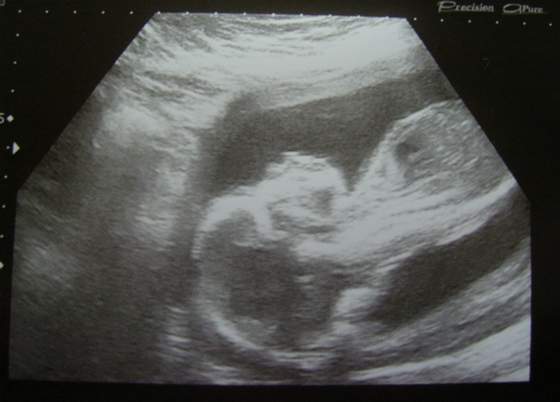

Od niego będzie zależało, czy urodzę normalnie, czy będzie przymusowa cesarka...